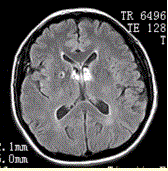

问题 男性,55岁。临床偶尔头晕,无高血压,糖尿病病史。MRI显示如下图。 关于血管周围间隙,描述错误的是

选项 A.单层或多层柔脑膜包绕 B.邻近脑实质可见胶质增生 C.临床无症状 D.3T常见,各个年龄均可见 E.位于基底节区(前联合附近),其他常见位置:中脑,白质深部

答案 B